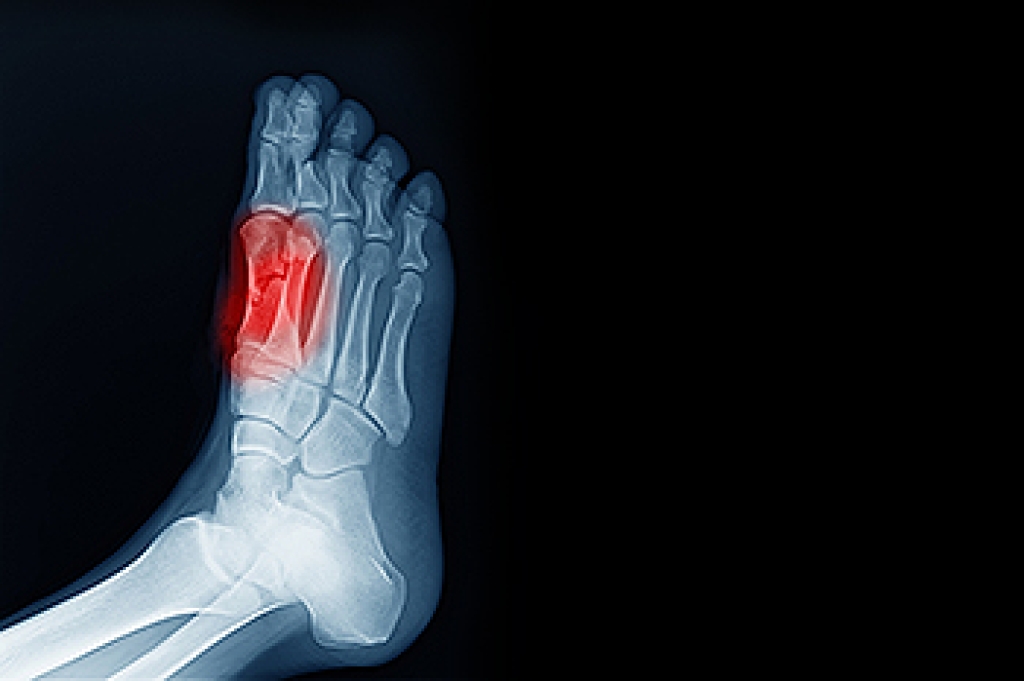

Plantar fasciitis is one of the most common causes of heel pain. The plantar fascia is a ligament that connects your heel to the front of your foot. When this ligament becomes inflamed, plantar fasciitis is the result. If you have plantar fasciitis you will have a stabbing pain that usually occurs with your first steps in the morning. As the day progresses and you walk around more, this pain will start to disappear, but it will return after long periods of standing or sitting.